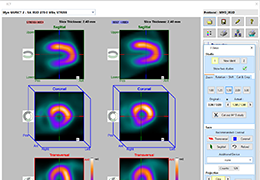

ANYTHINK 经导管主动脉瓣膜置换术分析系统